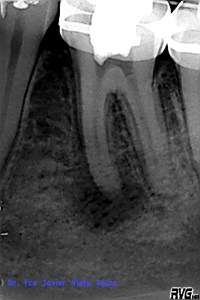

Presentaba una lesión periapical crónica, su diagnóstico es una necrosis pulpar con periodontitis apical crónica.

Le realizamos el tratamieto endodóntico del sistema de conductos en dos sesiones, soy un fiel defensor del medicameento intraconductos por varios motivos que quizás no sea el momento de comentar.